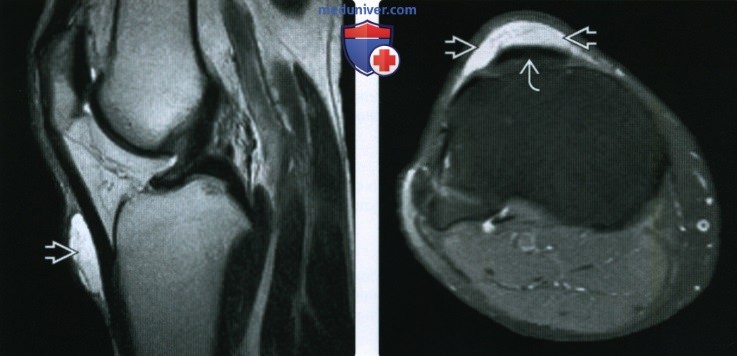

Заболевание сустава: симптомы и лечение

Раздел: Фотодневник открытий